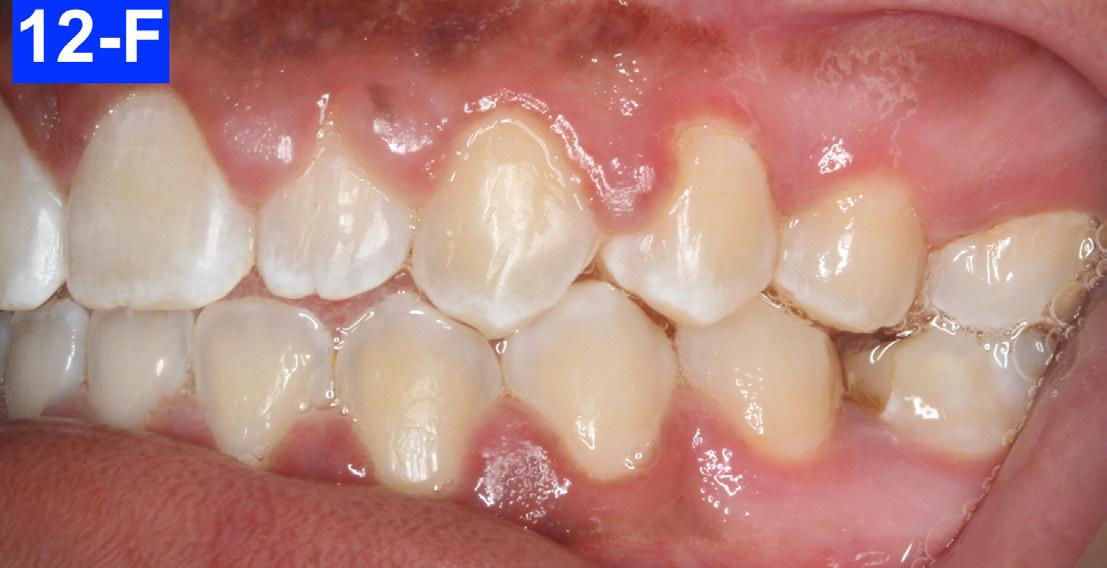

Figures 12-A to 12-M show the post-treatment images at the time of insertion of the retainers. We had an opportunity to evaluate the patient’s occlusion three years post-treatment. Compared to the initial post treatment evaluation, it was noted that the occlusion had settled into an even more stable position after three years.

Fig. 12-E: Post-treatment, right lateral view

Fig. 12-F: Post-treatment, right lateral view